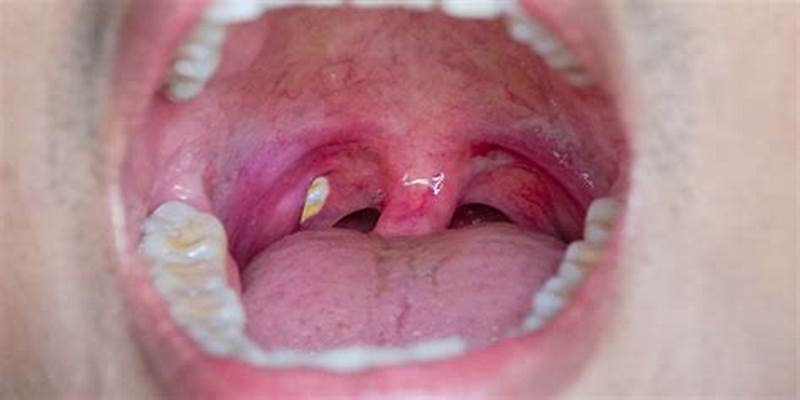

편도결석이란 편도결석은 편도에 생기는 작은 돌 같은 덩어리로, 편도내 세균, 단백질, 칼슘 등이 결합하여 생성됩니다. 이 글에서는 편도결석이 생기는 이유, 확인법, 증상, 냄새 방지법, 제거법, 가글법, 그리고 치료법에 대해 자세히 알아보겠습니다.

편도결석 확인법

편도결석을 확인하는 방법은 다음과 같습니다.

2. 혀를 사용한 확인

편도결석은 주로 편도의 맨 앞쪽에 생기기 때문에, 혀를 뒤로 내밀어 편도를 확인하면 쉽게 발견할 수 있습니다.